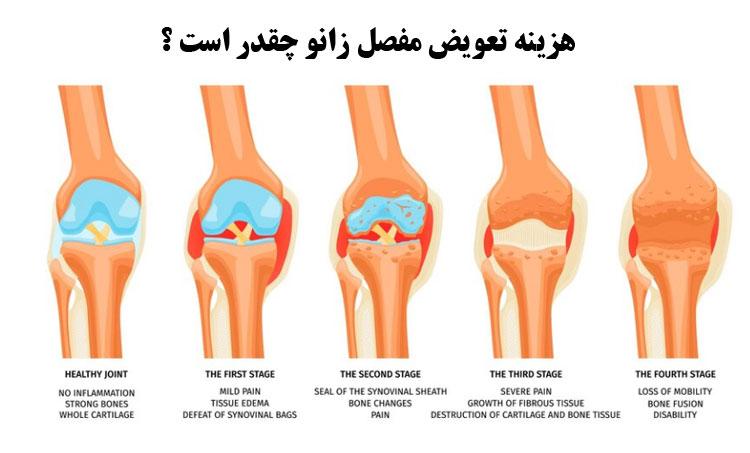

بیشترین مراجعه به متخصص و فوق تخصص زانو , زانو درد ناشی از ارتروز زانو است . لذا درمان جراحی زانو درد همواره یکی از مهمترین چالشهای علم ارتوپدی بوده است . استئوارتریت زانو یا همان ارتروز زانو و ساییدگی زانو شایعترین علت مراجعه به فوق تخصص زانو می باشد . امروزه جدیدترین و بهترین تکنولوژی درمان ارتروز زانو مورد استفاده بین جراحان فوق تخصص زانو استفاده از سلول های بنیادی بند ناف می باشد و تنها بیمارانی در کشورهای پیشرفته تحت جراحی تعویض مفصل زانو و لگن قرار می گیرند که به درمان با سلول بنیادی زانو پاسخ نداده باشند . امروزه بیش از 8000 کلینیک سلول درمانی زانو در امریکا وجود دارد .دکتر امین کامرانی راد با سابقه ی بیش از 1000 جراحی تعویض مفصل زانو .

جراحی تعویض مفصل زانو یکی از رایجترین عملهای جراحی مفاصله که معمولا برای درمان آرتروز شدید زانو انجام میشه.

تعویض مفصل زانو یک روش جراحی است که در آن مفصل زانوی آسیب دیده با مفصل مصنوعی جایگزین میشود. این روش برای درمان بیماریها و آسیبهایی مانند آرتروز (سایره) زانو، آسیبهای روماتولوژیکی، آسیبهای ورزشی شدید و آسیبهای ناشی از تصادفات استفاده میشود.

هزینه تعویض مفصل زانو و لگن

هزینه تعویض مفصل زانو به عوامل مختلفی بستگی دارد و ممکن است متغیر باشد. در ادامه، عواملی که میتواند بر هزینه تعویض مفصل زانو تأثیر بگذارد را بررسی میکنیم:

1. مکان و مرکز درمانی:

هزینه تعویض مفصل زانو بستگی به مکان و مرکز درمانی که انجام میشود، دارد. هزینه در بیمارستانهای خصوصی معمولاً بیشتر از بیمارستانهای دولتی است.

2. نوع مفصل مصنوعی:

هزینه تعویض مفصل زانو بستگی به نوع مفصل مصنوعی استفاده شده دارد. مفصلهای مصنوعی با کیفیت و فناوری بالاتر معمولاً هزینه بیشتری دارند.

3. هزینه عمل جراحی:

عمل جراحی تعویض مفصل زانو هزینهبر است. این هزینه شامل هزینههای جراح، نظارت پزشکی، بیهوشی و تجهیزات پزشکی است.

4. هزینه بستری در بیمارستان:

بستری شدن در بیمارستان پس از عمل جراحی تعویض مفصل زانو هزینهبر است و میتواند به طولانیتر شدن مدت بستری بستگی داشته باشد.

5. هزینه تجهیزات و تستها قبل از عمل:

قبل از عمل جراحی، تجهیزات و تستهایی نظیر آزمایشها، رادیوگرافی و اکوگرافی ممکن است نیاز باشد. هزینه این تجهیزات و تستها همچنین به هزینه کل تعویض مفصل زانو اضافه میشود.

6. هزینه جلسات توانبخشی:

برای بهبود و بازگشت به عملکرد طبیعی پس از عمل جراحی تعویض مفصل زانو، جلسات توانبخشی و فیزیوتراپی لازم است. هزینه این جلسات نیز در محاسبه کلیه هزینهها لحاظ میشود.

7. بیمه:

در صورت بیمهبودن بیمار، بیمه ممکن است بخشی از هزینه تعویض مفصل زانو را تحت پوشش قرار دهد. برای دقیقتر بودن، به بیمهنامه و قوانین بیمه خود مراجعه کنید.

با توجه به عوامل فوق، هزینه تعویض مفصل زانو متغیر است و به هر فرد و شرایط خاصی ممکن است متفاوت باشد. برای اطلاعات دقیقتر در مورد هزینه و مشاوره، بهتر است با یک پزشک متخصص مشورت کنید.